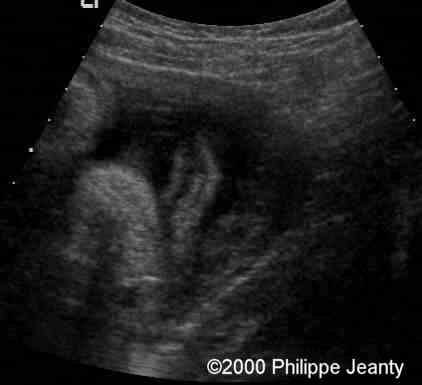

The other had both a simian crease and an unusual overlapping of the fingers viewed in this image and in the next (clinodactyly of the 5th finger)

case0020-4b

Other view of that same hand: note the clinodactyly.

case0020-5